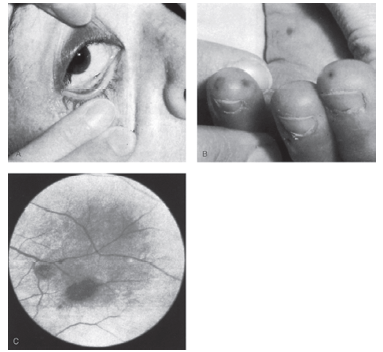

O conjunto de imagens abaixo representa o diagnóstico de:

Provas